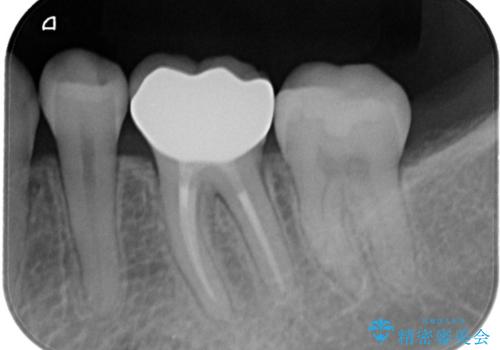

セラミッククラウンによる治療を希望されていたため根管治療から処置を行っています。

根管治療を行った歯には被せ物の治療がおすすめです。